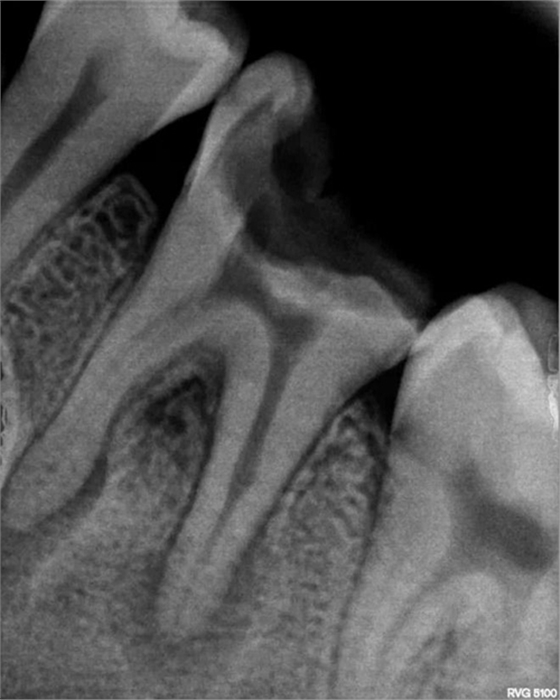

診斷、X片忽略,清潔患牙及鄰牙,對頜牙。

部分病例: